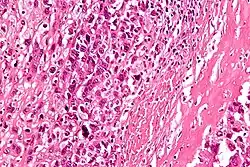

Mikroskopowo guz jest zbudowany z wrzecionowatych komórek, choć faktycznie cechuje go tendencja do znacznego pleomorfizmu i anaplazji, przez co komórki mogą przybierać różne formy. W większości przypadków stwierdza się dwa i więcej typów komórek tworzących nowotwór. Również jądro komórkowe cechuje znaczny pleomorfizm. Nowotwór z definicji wytwarza osteoid, ale również może wytwarzać tkankę chrzęstną lub włóknistą. Ze względu na dominującą substancję pozakomórkową klasyczny kostniakomięsak może być dalej dzielony na postać osteoblastyczną, chondroblastyczną i fibroblastyczną[20][46].

Postać osteoblastyczna stanowi około połowy przypadków klasycznych kostniakomięsaków u ludzi[20][46]. Substancja pozakomórkowa tworzy cienką sieć pomiędzy pojedynczymi komórkami nowotworowymi. Nowotwory różnią się strukturą i gęstością substancji pozakomórkowej[47], która może być reprezentowana wyłącznie przez niezmineralizowaną osseinę do obecnych gęstych, zmineralizowanych beleczek kostnych. W części przypadków w utkaniu nowotworu przeważa substancja pozakomórkowa i komórki nowotworowe występują w niewielkiej ilości[46].

Postać chondroblastyczna stanowi około 25% przypadków klasycznych kostniakomięsaków u ludzi. W tym podtypie podstawową substancją pozakomórkową jest tkanka chrzęstna przypominającą chrząstkę szklistą przemieszaną z elementami niechrzęstnymi. Chrząstka jest zorganizowana w zraziki zawierające pojedyncze komórki z zaznaczoną anaplazją zlokalizowane w lukach pomiędzy substancją pozakomórkową. W obwodowej części guz staje się bogatokomórkowy[46]. Kostnina jest ubogo reprezentowana i może być obecna pomiędzy wrzecionowatymi komórkami a chrzęstnymi zrazikami[46][47].

Postać fibroblastyczna stanowi około 25% przypadków klasycznych kostniakomięsaków u ludzi. Jest to podtyp charakteryzujący się obecnością wrzecionowatych komórek z niewielką ilością substancji pozakomórkowej i obecność osteoidu jest bardzo uboga[48][49]. Utkanie może przypominać włókniakomięsaka lub niezróżnicowanego mięsaka pleomorficznego (malignant fibrous histiocytoma)[50].